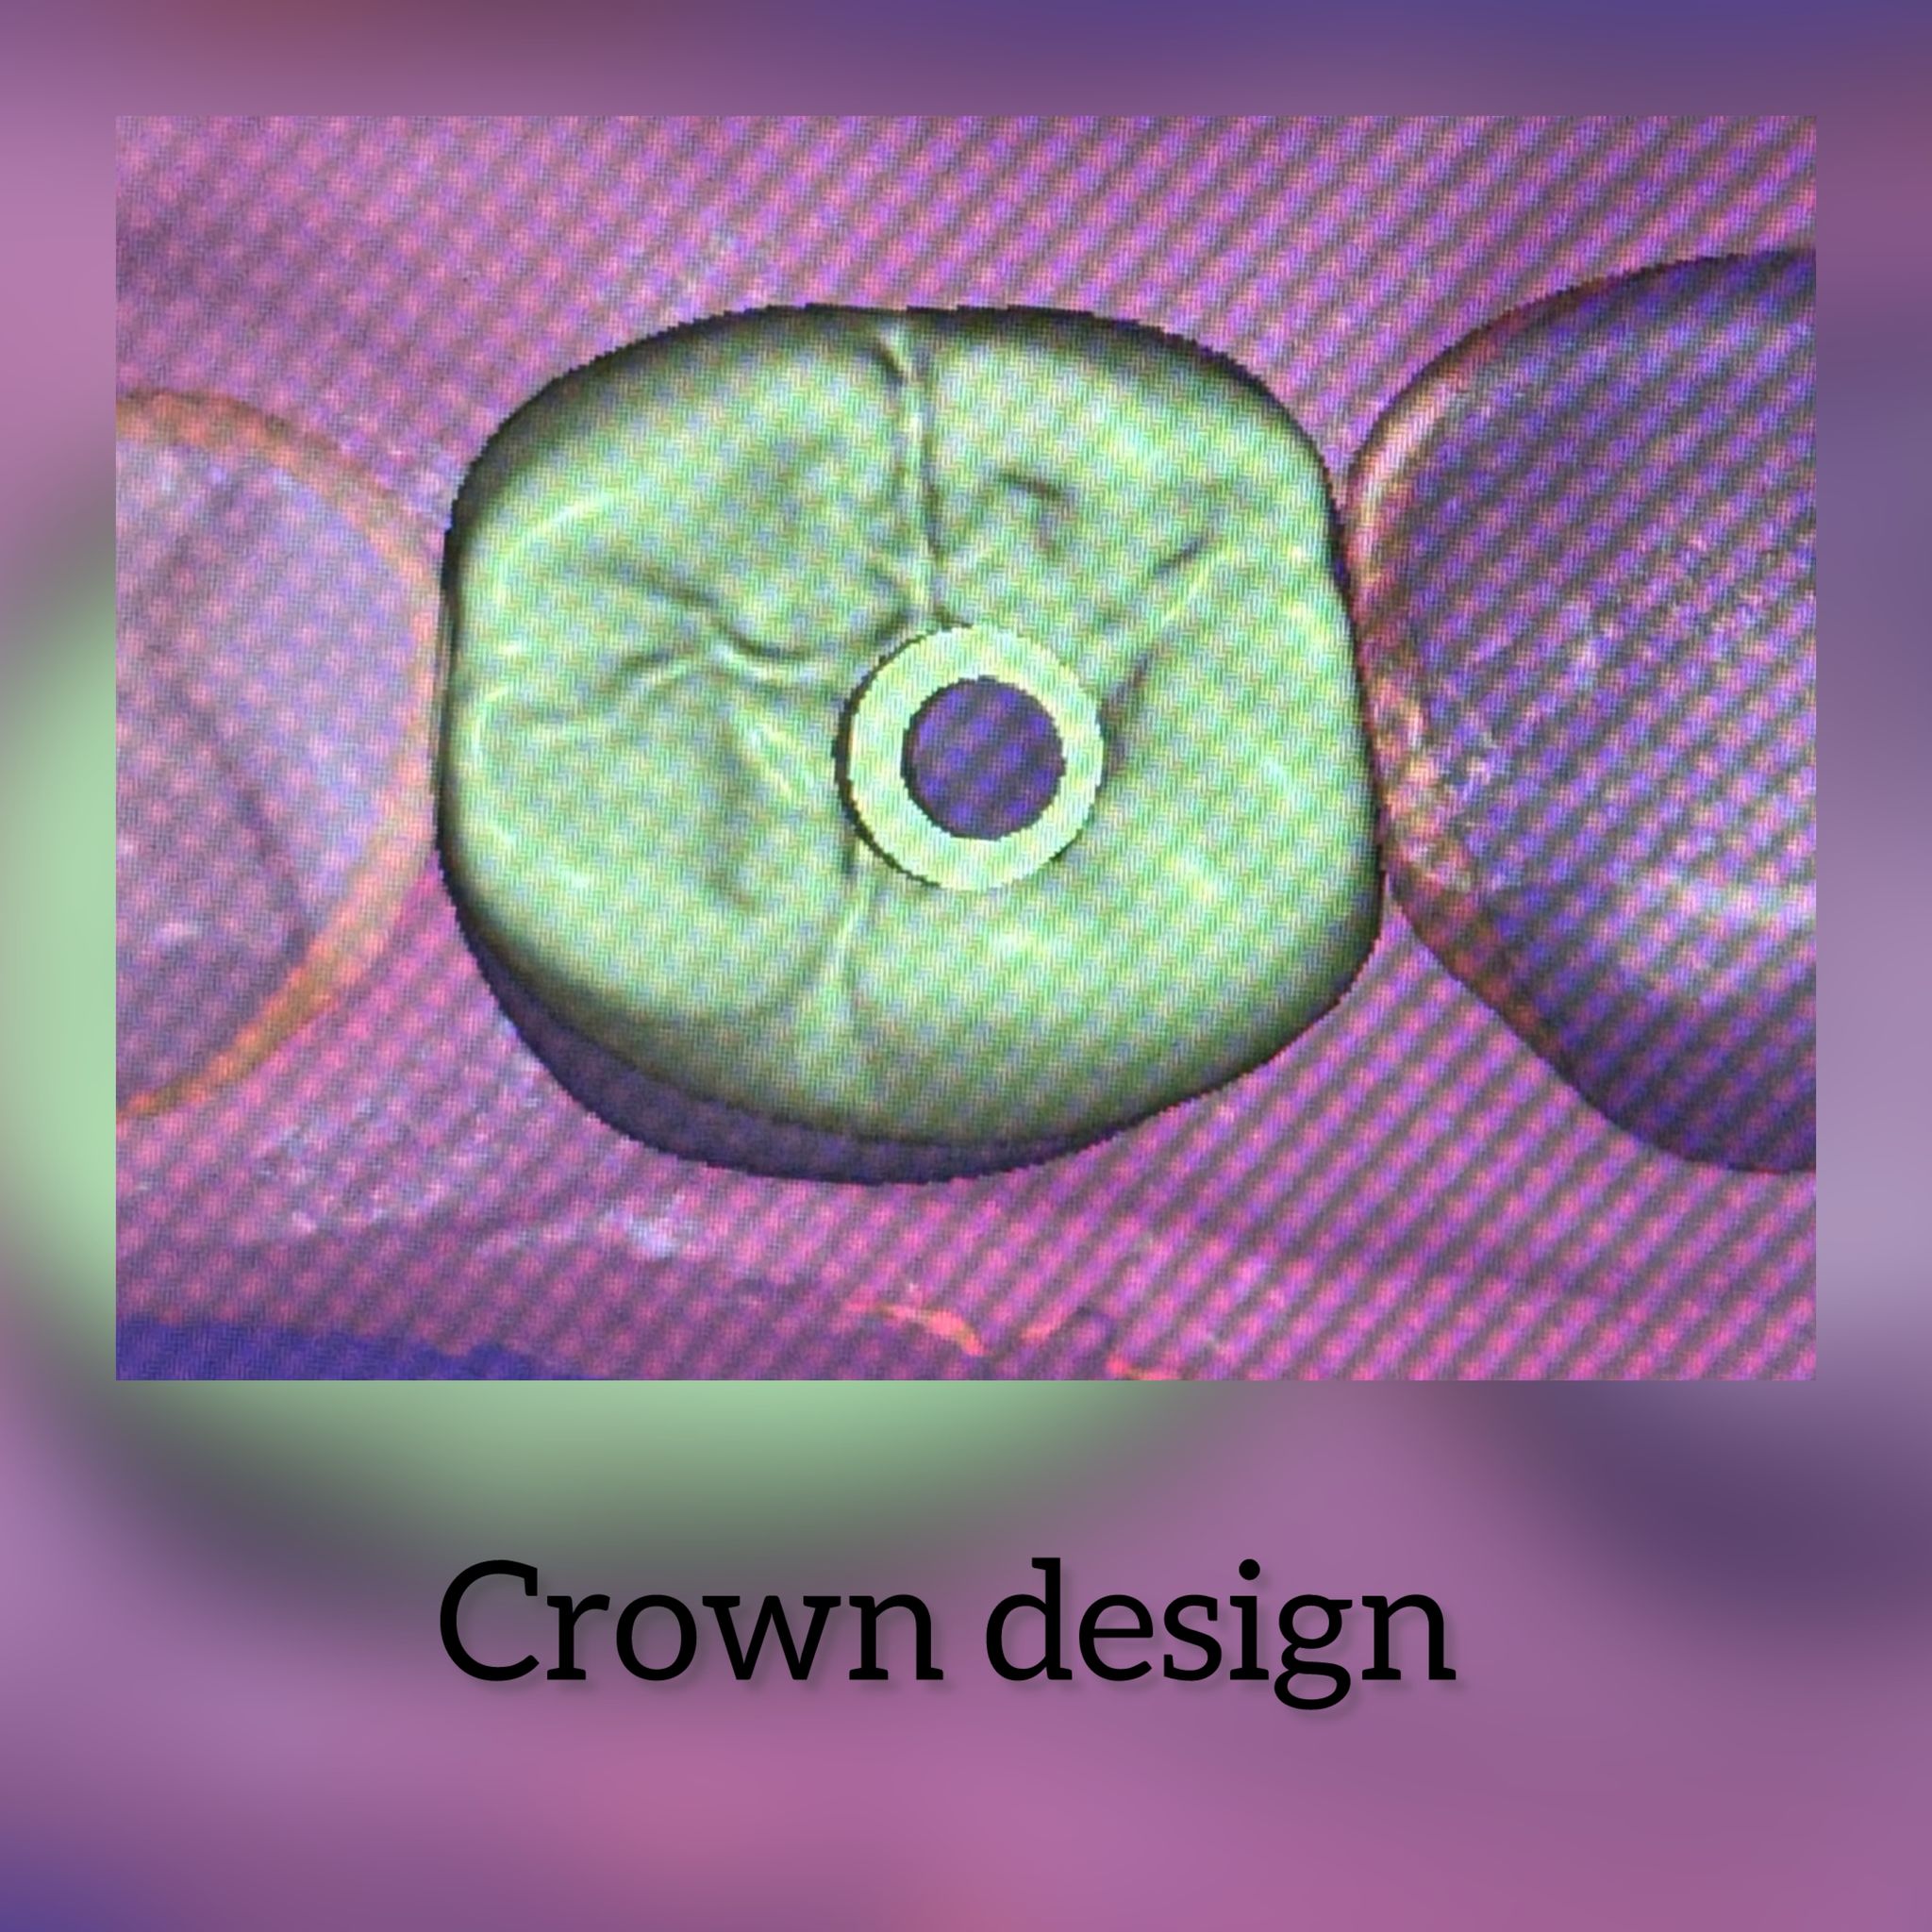

Dental Laboratorium in Amsterdam

Dental Laboratorium in Amsterdam